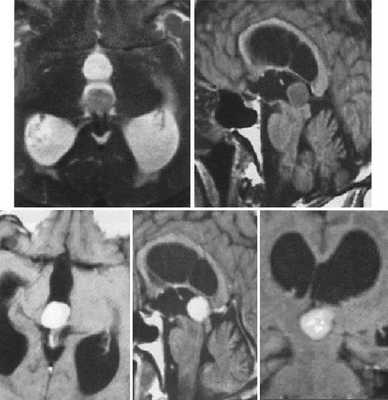

Пинеоцитома. На Т2 ВИ опухоль состоит из двух участков разной интенсивности МР-сигнала: высокой в передних отделах и низкой в задних. Четкость и линейность перехода свидетельствует о кистозном характере строения опухоли. Различия интенсивности МР-сигнала от жидкости в передних и задних отделах опухоли обусловлены эффектом «седиментации» белковых компонентов (вероятнее компонентов крови), опускающихся вниз при положении головы пациента на затылке.

Пинеоцитома. МРТ в режиме Т2 и Т1 выявляется солидного строения опухоль задних отделов III желудочка мозга. На фоне в/в контрастирования определяется выраженный и достаточно гомогенный характер контрастирования опухоли.

Пинеобластома. В режиме Т2 и Т1 выявляется опухоль задних отделов III желудочка мозга с развитием окклюзионной гидроцефалии. В строме опухоли небольшой участок подострого кровоизлияния. После в/в контрастирования опухоль интенсивно и достаточно гомогенно накапливает контрастирующее вещество.

Пиллоидная астроцитома задних отделов III желудочка. Определяется небольших размеров образование с развитием окклюзионной гидроцефалии. Опухоль практически не отличается по сигналам от вещества головного мозга. После в/в контрастирование отмечается усиление МР-сигнала от образование, что позволяет уточнить расположение опухоли, степень компрессии четверохолмной пластинки и водопровода мозга.

Глиобластома зрительного бугра справа. До и после в/в контрастирования определяется объемное образование с некротическим центром и контрастируемой периферической инфильтративной частью. Деформированы задние отделы III желудочка, начальный проявления окклюзионной гидроцефалии.

Эпендимома задних отделов III желудочка. Определяется объемное образование в задних отделах шишковидной железы. Передние бугорки четверохолмия оттеснены вниз. Водопровод мозга сдавлен.

Киста эпифиза. Компрессия четверохолмной пластинки и частичное сдавление водопровода мозга.